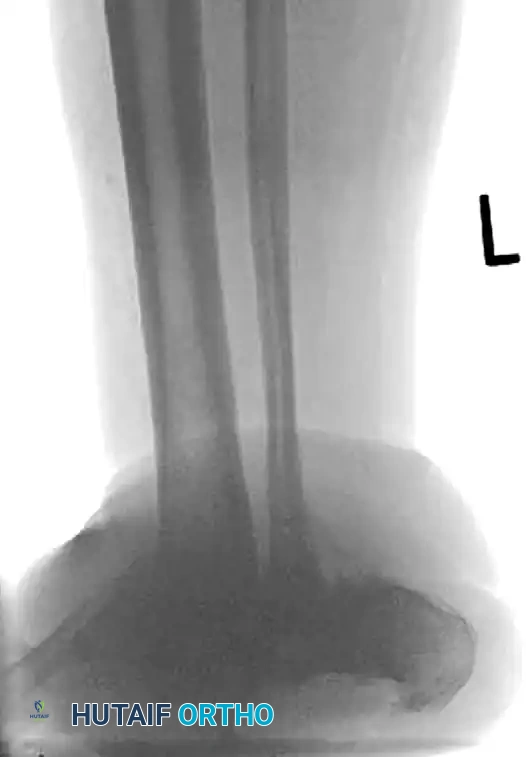

FIGURE 85-25 C-E: Postoperative fixation demonstrating robust fibular plating, medial malleolar screw fixation, and critical supplemental syndesmotic screws to reinforce the mortise.